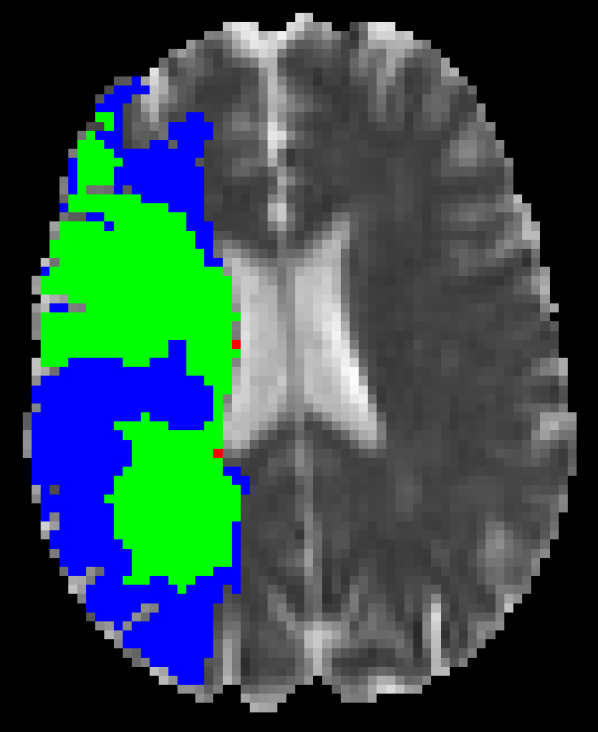

Figure 5 shows qualitative results of four representative segmentation examples from the proposed method. In general, the majority of the lesion is correctly segmented with minor border and small hole inaccuracies as seen in cases 11 and 26. Other less typical errors include under or oversegmentation of the lesion, as seen in case 2 where false positives are found on the upper part of the lesion. In the example of case 15, the lesion is undersegmented due to a confounding unusual appearance of some parts.

Figure 5: Output segmentation masks of representative cases from the training images of ISLES 2015 SPES dataset. On all images, true positives are denoted in green, false positives in red and false negatives in blue.